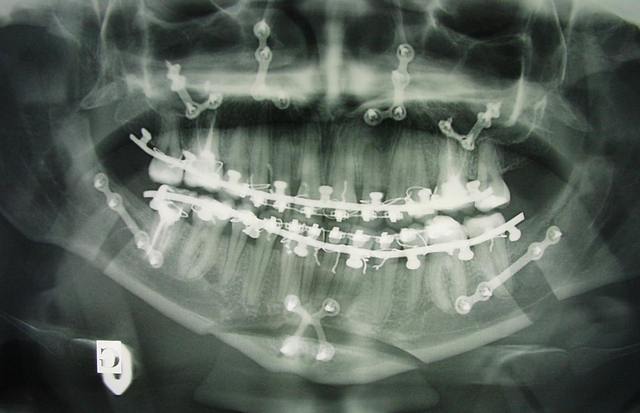

voici les radios de ma chir, j'aurais les photos lundi pour ceux que ça intéresse.

les photos avant, après 1 semaine et après 1 mois et 10 jours.